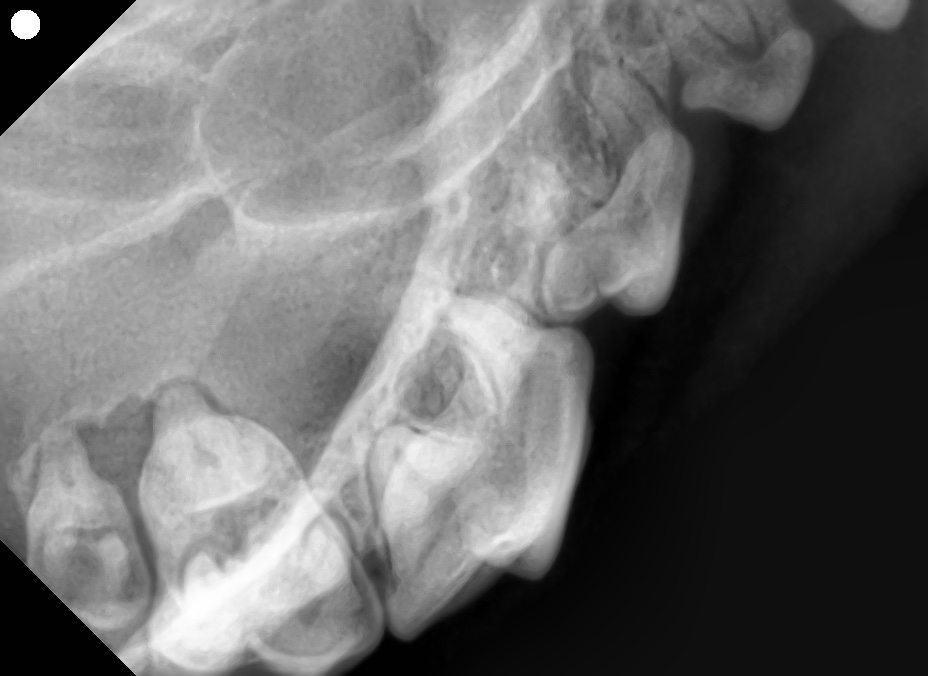

レントゲンでわかること

肉眼では歯石や歯肉炎程度に見えても、歯科レントゲンを撮影すると歯槽骨の融解(骨が溶ける変化)が進んでいるケースが多いです。

とくに上顎の奥歯は鼻腔や眼窩に近く、口腔鼻腔瘻(こうくうびくうろう)や眼の下の膿瘍につながるリスクがあるため注意が必要です。